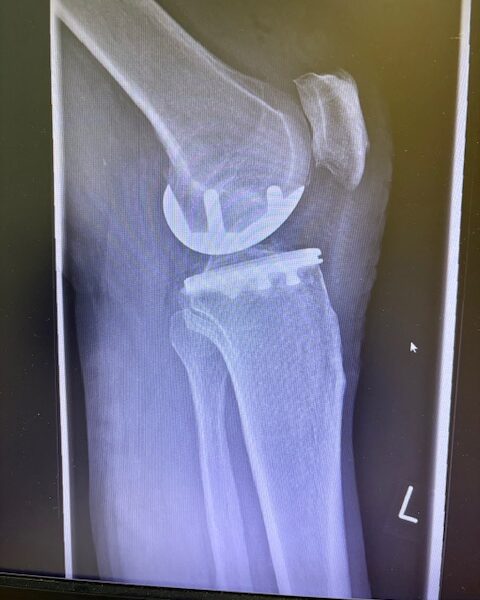

Η επέμβαση πραγματοποιήθηκε με ελάχιστα επεμβατική προσπέλαση και τοποθέτηση πρόθεσης μόνο στον έσω μηροκνημιαίο διαμέρισμα του γόνατος.

Η ακριβής προσαρμογή του εμφυτεύματος επιβεβαιώθηκε διεγχειρητικά, εξασφαλίζοντας σταθερότητα και φυσική κίνηση της άρθρωσης.

Στον ασθενή τα εμφυτεύματα που χρησιμοποιήθηκαν είναι της εταιρείας Zimmer-Biomet Persona Μηριαίο μέγεθος 6, κνημιαίο μέγεθος Η και ενθέμα (inlay) Η li. 8mm.